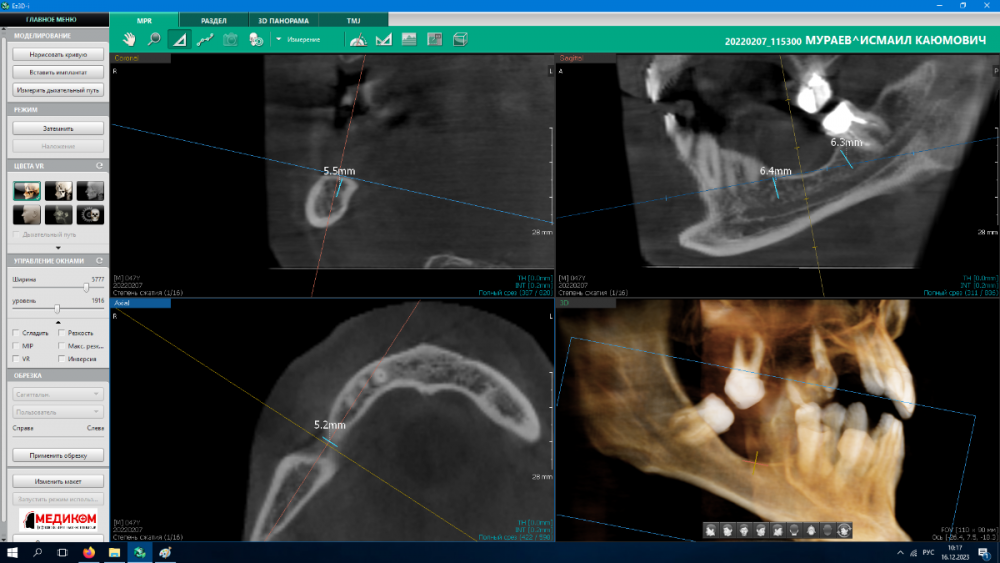

Bibars Опубликовано 16 декабря, 2023 Поделиться Опубликовано 16 декабря, 2023 (изменено) Здравствуйте. Уважаемые доктора, подскажите, пожалуйста. Пациент и. 49 л требуется полная реабилитация. 14, 27, 37, 38, 42, 48 периапикальные изменеия. Хочу сохранить 17, 42. План примерно следующий: установить импланты в области 13, 14,16 24, 25, 28, 35, 37, 38. Не уверен что делать с 4 квадрантом? в голове 2 варианта 1)Подсыпать кость 2) установить коротыши Anyridge . Если есть какие то дополнения, замечания, прошу поправьте . Если нужны еще какие то срезы ССылка на кт https://disk.yandex.ru/d/VS0gWCBpR_Mq9w Изменено 16 декабря, 2023 пользователем Bibars Ссылка на комментарий

Irouil Опубликовано 16 декабря, 2023 Поделиться Опубликовано 16 декабря, 2023 1 прячьте личные данные пациента, он Вам за это спасибо не скажет 2 если Вы всерьёз рассматриваете вариант "подсыпать кость" в таких условиях - точно не подсыпАть 3 для безопасной работы тут нужны импланты 4-4.5 мм, ЕМНИП у эниридж 5.5 мм, так что лучше рассмотреть ТЛ 4 если супракрестальной аугментацией и ТЛ имплантацией не владеете - я бы нашёл доктора, который владеет, договорился бы на референс пациента за право поприсутствовать на операции 1 4 Ссылка на комментарий